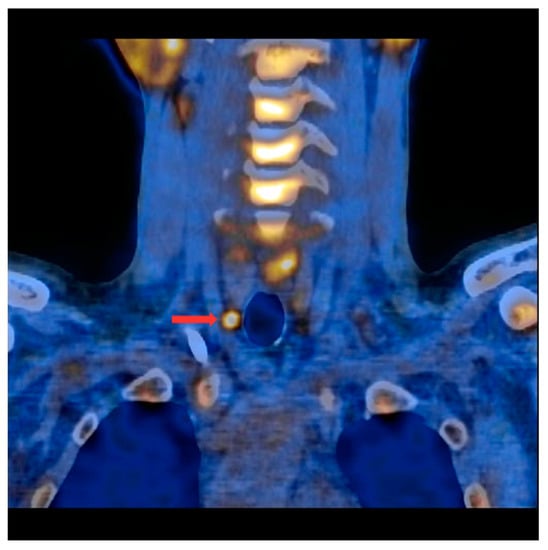

Figure 1.

PET/CT with [11C]MET—frontal projection. Visible focus of increased radiotracer accumulation (red arrow) corresponding to the parathyroid gland below the right thyroid lobe.